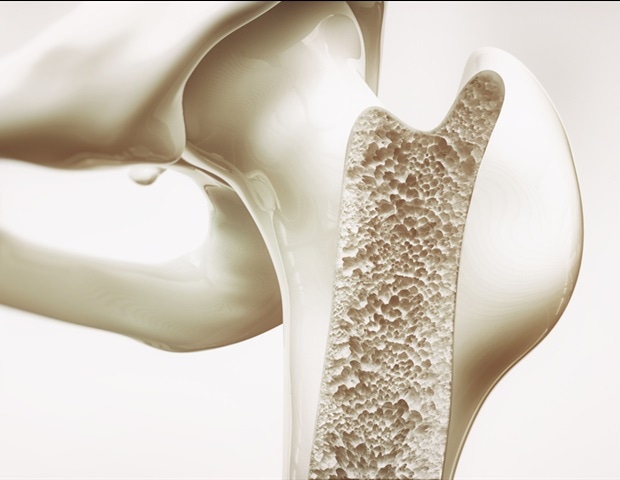

אוסטאופורוזיס היא מחלה בה העצם מתפוגגת מהר יותר מכפי שהיא נוצרת, ומיחשת בהדרגה את מבנהו לאורך זמן ומובילה לשברים. אף